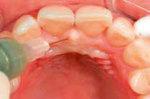

Patientensituation nach erfolgter Therapie mittels Metronidazol, CHX Chips, aPDT und anderen Maßnahmen nach dem 3. Recall

Applikation des OXYSAFE Gels in situ Patientensituation 3 Wochen nach Beginn der Sauerstofftherapie mittels OXYSAFE

Anwendung von OXYSAFE®

Beispielhaft nun die Anwendug von OXYSAFE am Frontzahn

11. Die Sondierungstiefe beträgt sowohl mesial als auch distal 7 mm an Zahn 11 und es liegt eine Blutung vor. Es liegt ein vertikaler Knochenverlust vor.

Reinigen der Zahnfleischtasche Erste direkte Applikation des Gels in die Zahnfleischtasche Fortsetzung der Behandlung durch den Patienten zuhause 3 täglich 10 ml Zweite Applikation des Gels in die Zahnfleischtasche und dort belassen >> Keine Antibiotika >> Kein CHX >> Über 20 Jahre klinische Erfahrung ca. 2,74 € pro Zahnfleischtasche Aktion Jetzt gratis testen!*